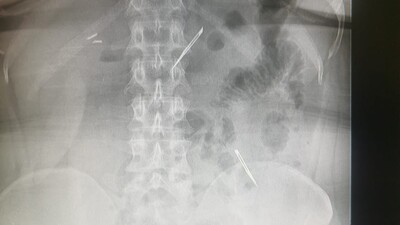

Sağlık Bilimleri Üniversitesi Ankara Atatürk Sanatoryum Eğitim ve Araştırma Hastanesi’ne mide ve karın bölgesinde aşırı ağrı şikayetiyle müracaat eden 46 yaşındaki D.E.’nin yapılan tahlil, tetkik ve çeşitli görüntülemelerden sonra bağırsak kısmında 2 adet neşter olduğu tespit edildi.

Genel cerrahi kliniği tarafından zorlu bir ameliyat sonrasında neşterler kadının vücudundan çıkarıldı. 46 yaşındaki D.E. neşterleri nasıl yuttuğunu bilmediğini tahminen ekmekle birlikte yutabilmiş olabileceğini ifade etti. Ameliyatı gerçekleştiren Sağlık Bilimleri Üniversitesi Ankara Atatürk Sanatoryum Eğitim ve Araştırma Hastanesi Genel Cerrahi Kliniği Eğitim ve İdari sorumlusu Prof. Dr. Hakan Buluş ise hastanın yoğun şikayetleri üzerine çektikleri röntgen sonrasında 2 adet neşteri görünce şaşkına uğradıklarını söyledi.

Hastanın şikayetlerinin artması üzerine gerçekleştirilen tetkiklerde 46 yaşındaki kadının karın bölgesinde 2 adet yabancı cisim olduğunu tespit ettiklerini, detaylı inceleme sonucunda bu cisimlerin neşter olduğunu fark ettiklerini belirten Prof. Dr. Buluş, “Yaklaşık 10 gün önce kliniğimize karın ağrısı ve bulantı şikayetleriyle başvurdu. Bizim yaptığımız fiziki muayene ve tetkiklerinde hastanın direkt karın grafisinde 2 adet yabancı cisim olduğunu tespit ettik. Aslında yabancı cisim bizim güncel grafiğimizde sık karşılaştığımız bir durum değil, fakat nadir de olsa görebildiğimiz bir patoloji. Biz de bunun üzerine ayrıntılı değerlendirmeler ve tetkikler yaptık. Sonrasında 2 adet yabancı cismin bistüri (neşter) ile uyumlu olduğunu gördük. Bunun üzerine hastanın şikayetlerinin de artması üzerine, ameliyat kararı verdik. Yaptığımız ameliyatta ince bağırsağın yaklaşık 180’inci santimetresinde bu yabancı cisimlerin olduğunu tespit ettik. Bunun üzerine ameliyatla bunları çıkarttık. Hastamızın sağlık durumu şuan gayet iyi. Ameliyattan sonraki üçüncü günü. Şuan bir problemi yok, inşallah birkaç gün içerisinde şifa ile taburcu etmeyi düşünüyoruz” şeklinde konuştu.

Çıkardıkları cismin, neşterin normalde ameliyatlarda kullanılan bir malzeme olduğunu söyleyen Prof. Dr. Buluş, “Çıkardığımız yabancı cisimler bizim ameliyatlarda sıkça kullandığımız 11 numara dediğimiz bir bistüri tipi. Ebatları da yaklaşık 4 santime yarım santim ebatlarında. Ucunun sivri olması nedeniyle ince bağırsak mukozasına saplanarak enflamasyon ve bir karın ağrısı yapması, sonrasında da ağrı şikayetlerinin artmasına neden olmasından dolayı ameliyat kararı verdik” diye konuştu.